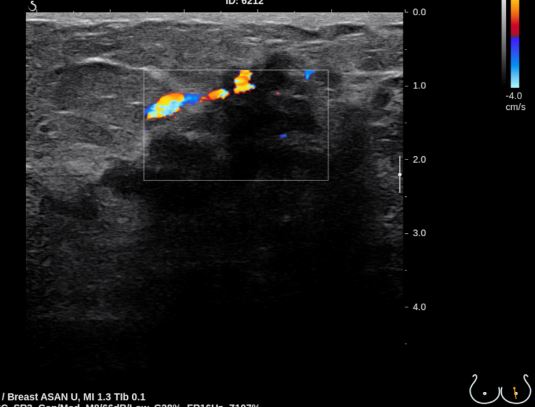

상기환자 건강검진상 이상소견으로 내원 하신 50대 여성분으로 좌측 유두밑 의심스러운 부분 조직검사 시행하여 좌측 침윤성 유관암 진단 되었습니다.